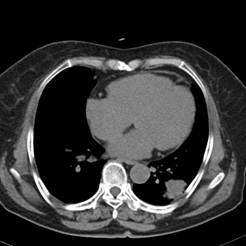

典型病例2:患者张XX,男,65岁,住院号:496686,因发热、胸闷、背痛2月余入院,体温最高达39℃,背部疼痛难忍。2015年6月29日胸部增强CT示:右肺下叶11.6cmx12.5cm巨大肿块,中心大片低密度坏死区,第8胸椎及右侧第8后肋骨转移。于7月2日行CT引导下穿刺活检术,病理证实为右肺鳞癌。给予125I放射性粒子植入治疗,术中首先利用植入针,穿刺肿块中央坏死区,连接引流袋后抽出肿瘤内坏死液体约500ml,抽液后肿瘤缩小约1/3;随后将125I粒子植入到第8胸椎体及第8后肋骨转移区,同时重点放置患侧滋养动脉供血区域。术后第二天,患者体温恢复正常;术后一周随访,患者背痛缓解。该患者出院回家,仍在随访中。

术前CT片